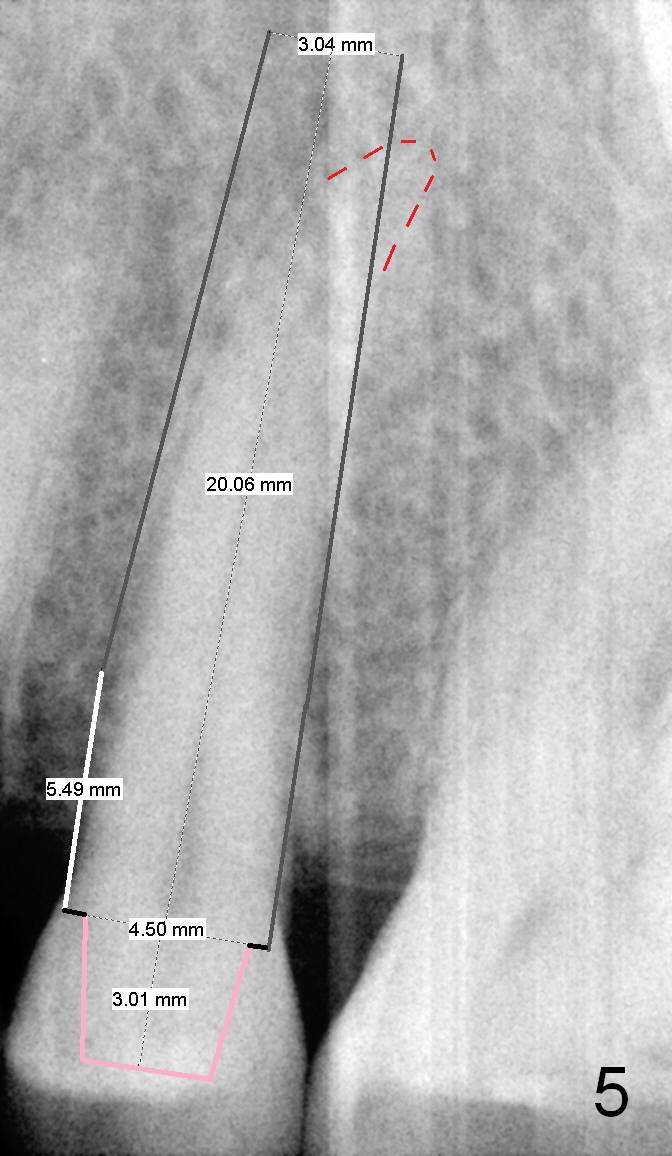

A 67-year-old lady (CC) has an implant at the site of #3, which replaces the fractured tooth (Fig.1). Recently the tooth #13 also fractures subgingivally (Fig.2). The tooth has a long and curved root. All of these suggest that the patient is a bruxer. The bone density is high. After extraction and placement of Clindamycin gauze in the socket, a 2 mm pilot drill is used to start osteotomy ~17 mm from the gingival margin, followed by 2.5 mm reamer ~ 17 mm, and 3 for 14 mm. If the socket looks small (mesiodistally), the goal is to place 4.1x14 (Fig.3) or 13 mm (Fig.4) implant. Otherwise use 4.5x17 mm Tatum tapered tap at 14 mm and plan to place a 4.5x13 or 14 mm implant. If it is difficult to insert an implant, use one size smaller drill from its original cassette or use 5x17 mm tap at 11 mm (to open up the entrance of the osteotomy). If the implant or tap is being deviated buccally while it is placed, use a Lindermann bur from Bicon Restorative plastic box to remove the bone from the palatal wall. When the side-cutting drill is cleaned, keep it in the Bicon Surgical Cassette. If the bone density turns out to be low, osteotomy depth will be 20 mm instead (Fig.5). When the flutes of 2.5 and 3 mm reamers collects bone particles, the bone density is high.